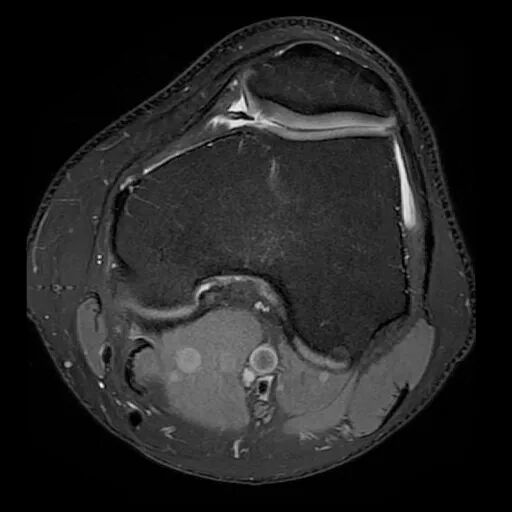

膝关节里那磨人的小妖精:滑膜皱襞(plica)综合症_膝关节损伤_发病原因

卡住的膝关节之三---内侧滑膜皱襞综合征_膝关节损伤_膝关节损伤介绍

时是膝关节内侧痛,经mri和关节镜确诊为内侧半月板损伤,内侧滑膜皱襞

膝关节内多出来一片滑膜皱襞

膝关节疼痛上下楼梯困难要当心膝关节滑膜皱襞综合征

上,下楼梯时膝内侧疼痛?快来检查一下你的滑膜皱襞吧